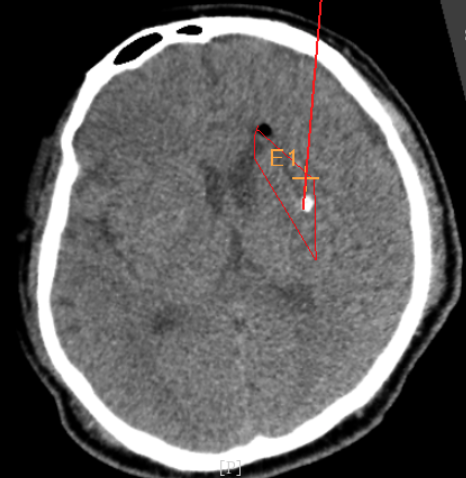

術(shù)前CT:血腫已經(jīng)液化,但仍有占位效應(yīng)

手術(shù)日當(dāng)天,醫(yī)生團隊通過手術(shù)計劃系統(tǒng)為患者制定手術(shù)靶點及最安全的入顱路徑,隨后將手術(shù)規(guī)劃導(dǎo)入手術(shù)室的機器人當(dāng)中。

術(shù)前韓帥醫(yī)生使用“睿米”制定手術(shù)規(guī)劃

手術(shù)規(guī)劃在機器人軟件上制定完成